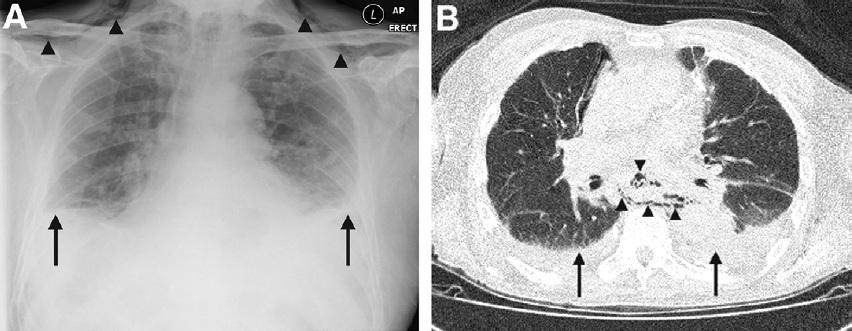

一名年龄84岁的老年男性因急性左侧胸痛、近期腹泻呕吐而来到急诊室。他患有严重阿尔茨海默病性痴呆,住在长期护理机构。在到达急诊室时,该患者无法清晰表述病史,并且因胸痛而非常痛苦。检查显示,锁骨上皮下气肿,肺底进气量减少。实验室检查显示,白细胞增多(29.7×103/L)、急性肾衰竭(血尿素氮59.5 mg/dl,肌酐2.2 mg/dl)。胸部X线片(图A)证实皮下气肿(三角箭头),并且提示双侧胸膜积液(长箭头)。胸部CT(图B)显示纵隔气肿(三角箭头)和双侧胸膜积液,左侧积液更多(长箭头)。

泛影葡胺吞咽检查(图C)显示,食管远端破裂,泛影葡胺漏至纵隔(长箭头)。上消化道内镜检查证实食管远端左后外侧壁破裂,符合Boerhaave综合征(图D),并置入1枚自膨胀覆膜支架。开始给予广谱抗生素治疗和鼻胃管饲养,行管状胸廓造口术对左侧胸膜积液引流。不幸的是,尽管初期病情有所改善,但该患者随后病情恶化,在入院后30天时死亡。